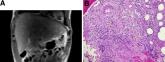

A man with HIV infection presented with jaundice, fever, and acute-onset left-upper quadrant abdominal pain.